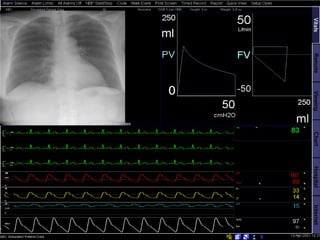

Servoventilator 300

Servo Screen 390

 Darstellung aller

Beatmungsparameter

online- inklusive aller

Meßmanöver und

gleichzeitiger

Trenderfassung

 Erstmals grafische

Darstellung der

Spontanatmung im

Langzeittrend

 Online- Darstellung eines

CO2- Respirogramm

 Integrierte

autodidaktische

Weiterbildung für

Anwender